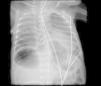

He was intubated after birth and received synchronized conventional mechanical ventilation from the 2nd minute of life. He needed surfactant administration three times, because of severe respiratory distress syndrome (RDS). On day (D) two of life he presented a pulmonary hemorrhage. On D17 he was moved from SIPPV+ volume guarantee (maximum settings: InspP=24cmH2O; frequency=60min–1; PEEP=5cmH2O; FiO2=0.6; VG=6.5ml/kg) to high frequency oscillatory ventilation (maximum settings: MAP=18; DeltaP=38; iT=33%; Freq=15Hz; FiO2=1). Blood cultures were negative as was reactive C protein. A 10 days course of systemic dexamethasone was started. Large cystic pneumatoceles appeared in the right and left lower lobe on D19 (Figs. 1 and 2). Taking a wait and see attitude, the pneumotoceles spontaneously regressed on D32 (Fig. 3).2 Serial cultures of tracheal aspirates from D15 became positive for an extended-spectrum beta-lactamase (ESBL) Klebsiella pneumonia strain, only sensitive to amikacin.